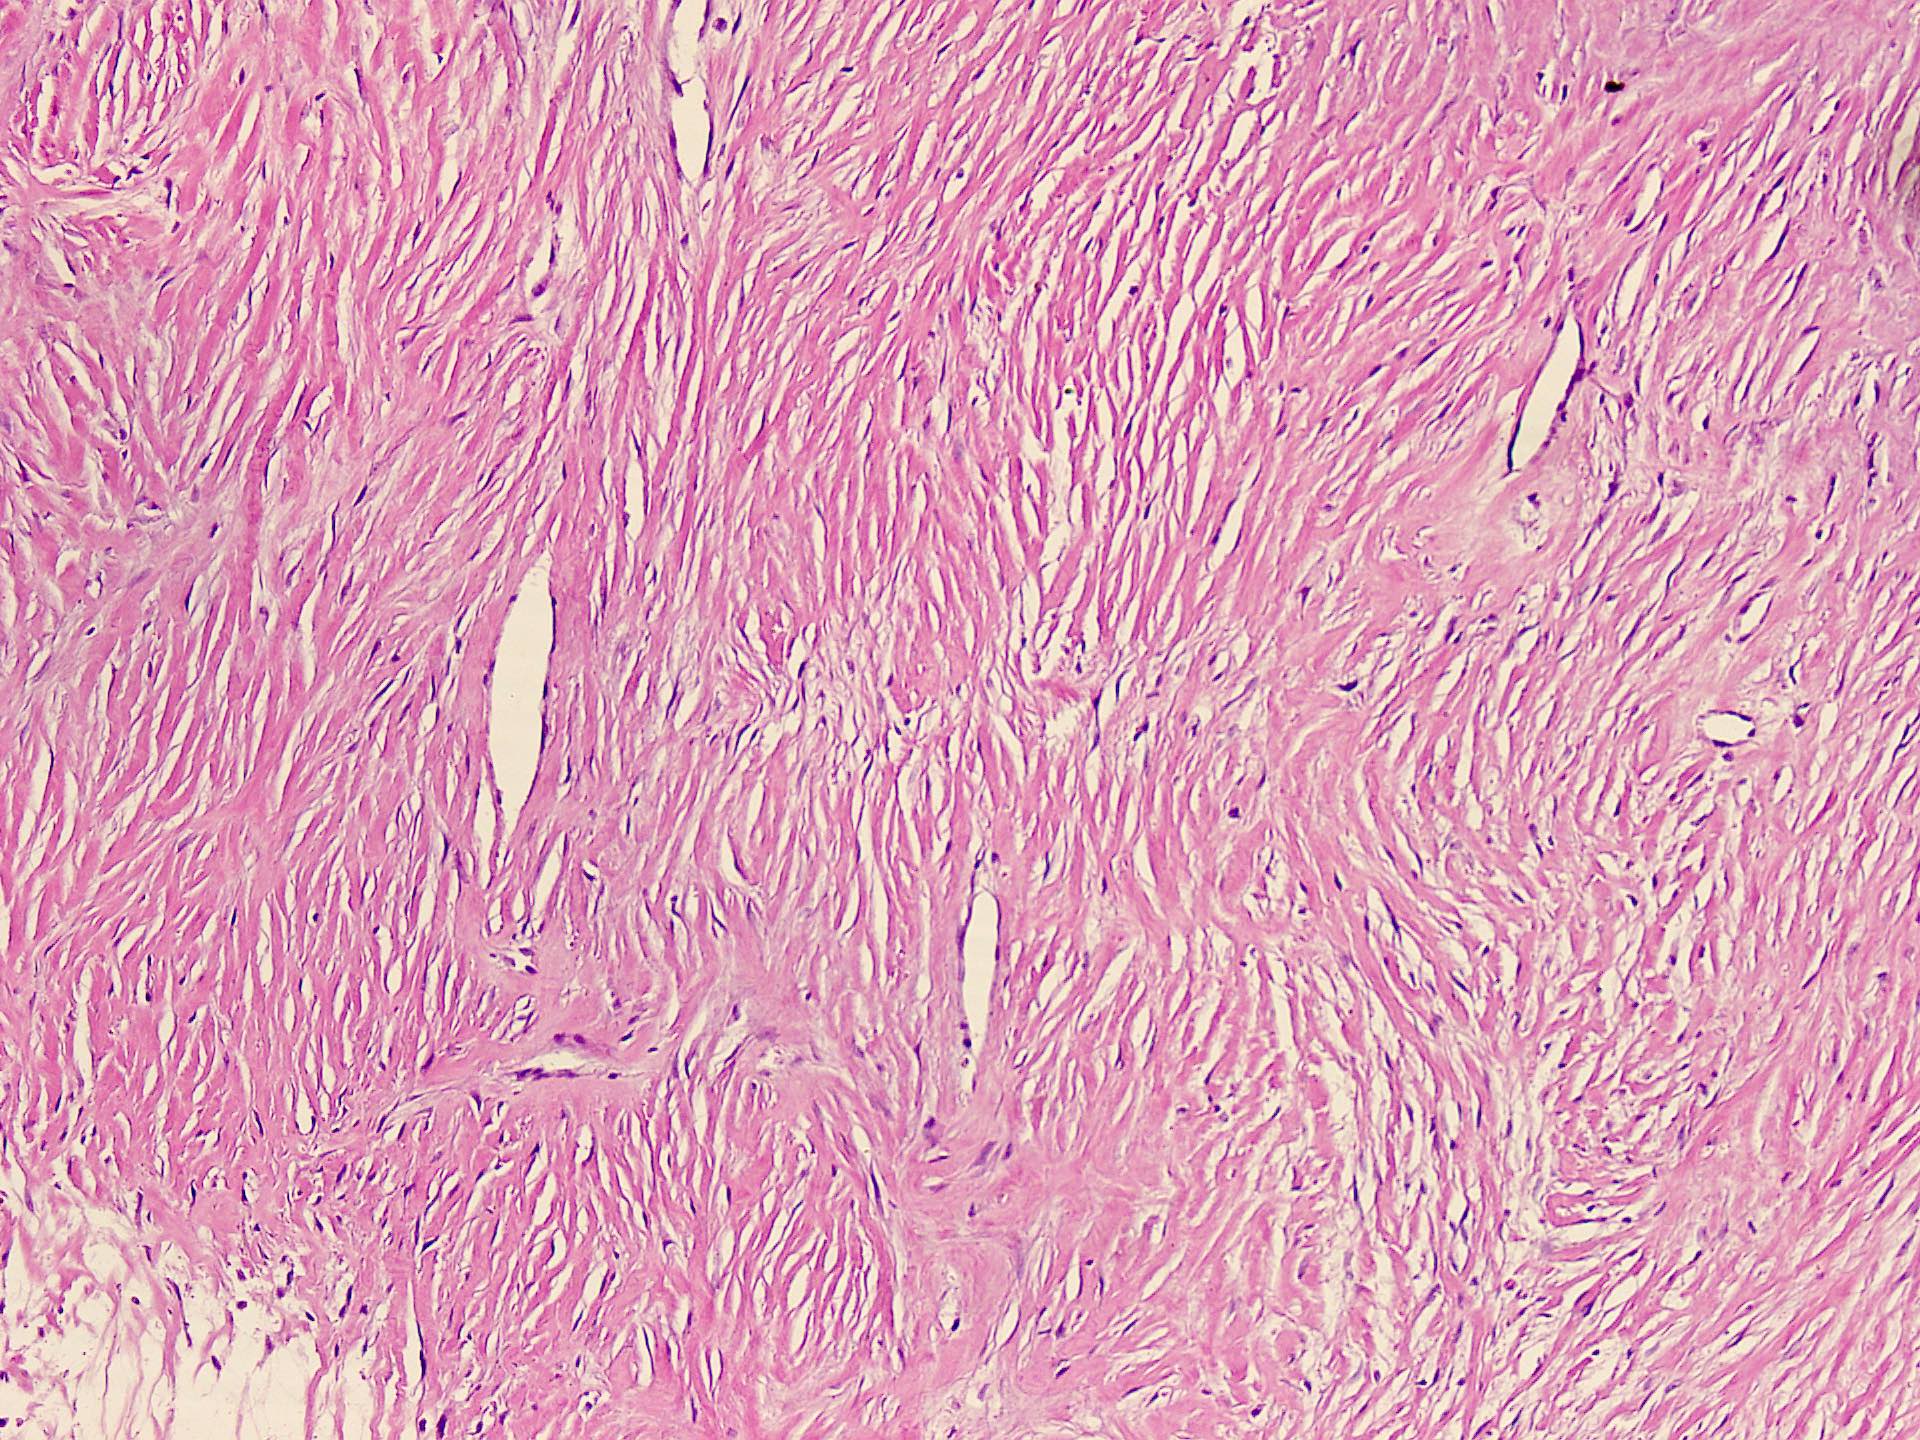

Microscopic (histologic) description

- Well circumscribed tumor of variable cellularity

- Cellularity mostly higher at tumor edges

- Bland spindle cells in a collagenous background

- Tumor has characteristic thin walled slit-like vessels

- Degenerative changes like myxoid / cystic change, osseous / chondroid metaplasia can be seen

- Bizarre pleomorphic cells can also be present

- Mitotically inactive

- Necrosis not present

- Cellular variant of fibroma of tendon sheath also exists; it overlaps morphologically with nodular fasciitis and fibrous histiocytoma (Cancer 1979;44:1945)

Microscopic (histologic) images

Contributed by Nasir Ud Din, M.B.B.S.

- Comment: Histology showed a well circumscribed, variably cellular lesion composed of bland spindle cells having regular nuclei arranged in sheets and fascicles. Thin walled vessels are present. The background is collagenous.

A 32 year old man has had painless swelling in the palm of his hand for 6 months. It was excised and the histology is shown in the above image. What is the most likely diagnosis?